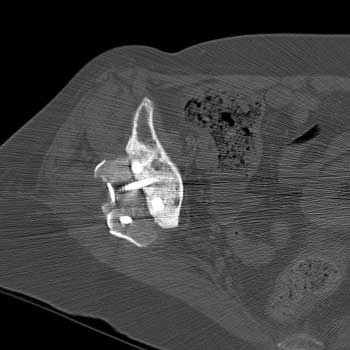

CT—Bone graft placed for patient with congenital hip dysplasia and poorly developed acetabulum (Shelf procedure). Persistent cleft between graft and native bone is present years after surgery, consistent failure of graft incorporation